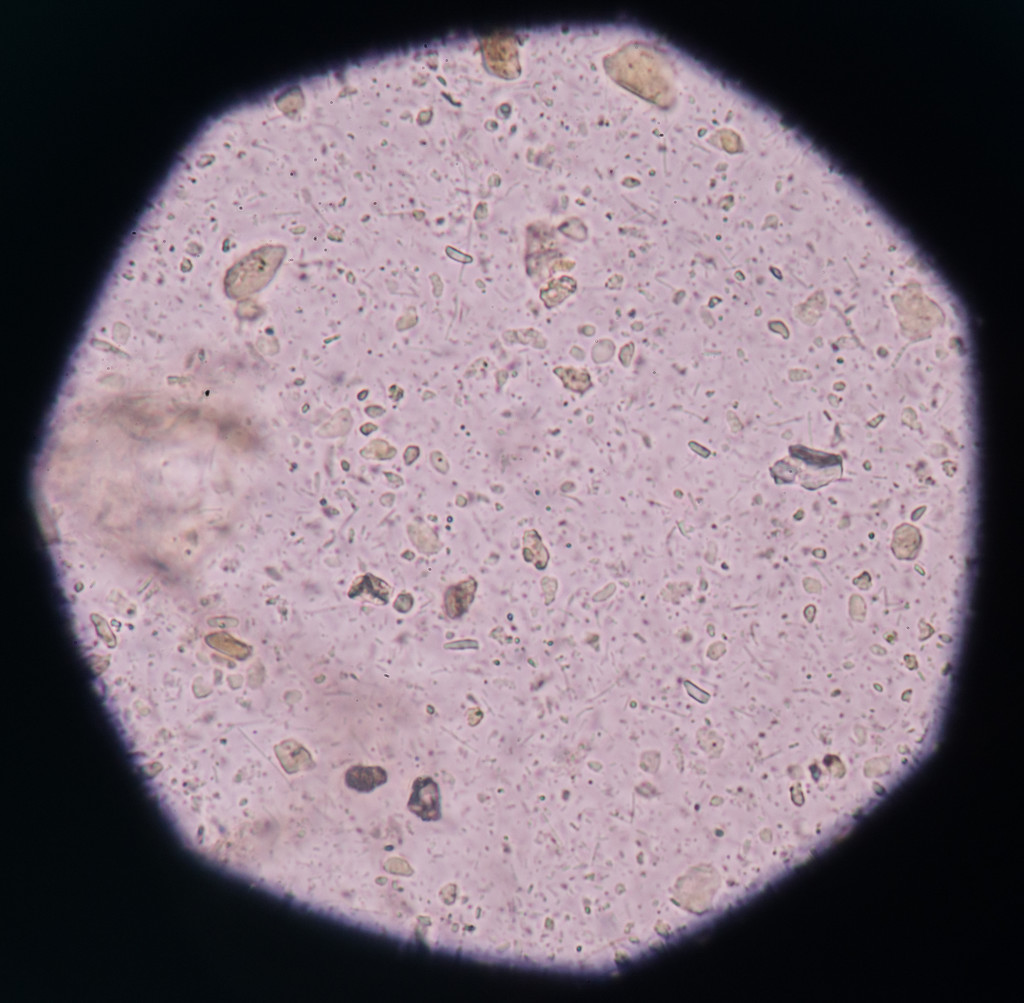

图司机为设计师提供高清在尿路感染的细图片版权下载,图片为科学技术,大小为7.17MB,尺寸为3957 x 3876px,更多关于微,健康,护理,发烧,单元格,考试,病人,测试,疾病,生物学,实验,实验室,化验室,真菌,分析,细菌,抗生素,研究,科学,有机体,性,显微镜,微生物学,传染性,道,感染,ευτυχισμένος άνθρωπος σε μαύρο χρώμα,尿,崭露头角,念珠菌,尿液分析,尿道,淋病奈瑟菌,念珠菌病,衣原体感染,上皮细胞,上皮,白带,泌尿道感染,尿道炎,trachomatis,yeast cells商用高清版权图片,快来图司机免费下载吧。